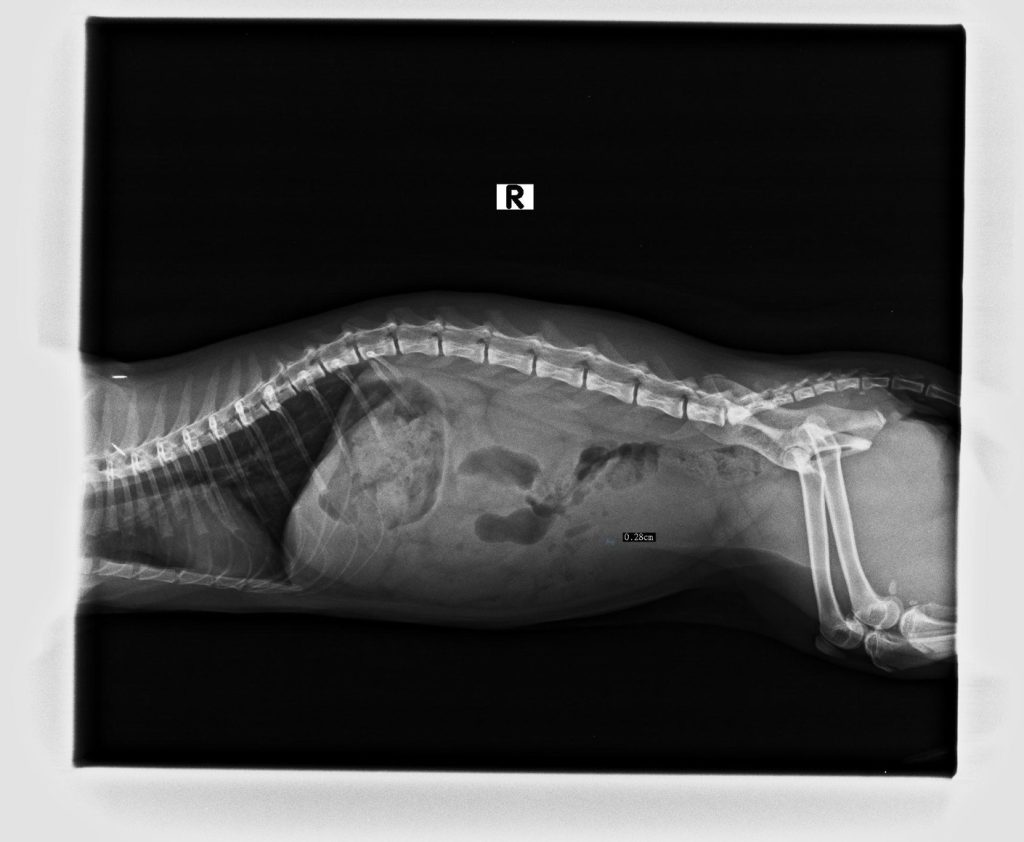

檢查階段

- X 光檢查:確認結石大小、位置及數量。

臨床檢查:X光下有一結石影像,超音波下也有結石影像。PH7.5,鏡下可見struvite結晶 。